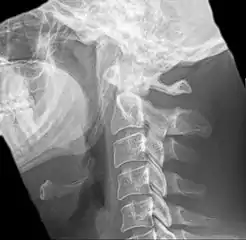

| Anteroposterior and lateral radiographs of cervical spine showing ossification of the stylohyoid ligament on both sides | |

Eagle syndrome (also termed stylohyoid syndrome,[1] styloid syndrome,[2] styloid-stylohyoid syndrome,[2] or styloid–carotid artery syndrome)[3] is an uncommon condition commonly characterized but not limited to sudden, sharp nerve-like pain in the jaw bone and joint, back of the throat, and base of the tongue, triggered by swallowing, moving the jaw, or turning the neck.[1] First described by American otorhinolaryngologist Watt Weems Eagle in 1937,[4] the condition is caused by an elongated or misshapen styloid process (the slender, pointed piece of bone just below the ear) and/or calcification of the stylohyoid ligament, either of which interferes with the functioning of neighboring regions in the body, such as the glossopharyngeal nerve.[4]